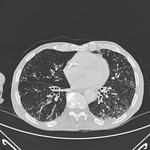

Chest x-ray of acute pulmonary edema showing increased alveolar markings, fluid in the horizontal fissure, and blunting of the costophrenic angles

From the private collections of Syed W. Yusuf, MBBS, MRCPI, and Daniel Lenihan, MD